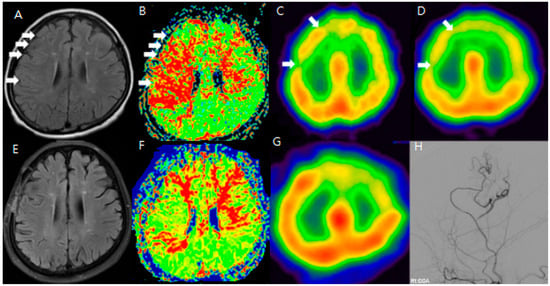

Among these patients, MR FLAIR and SPECT images were checked after the anastomosis (Figure 1).

To improve the analysis of preoperative and postoperative outcomes, the cerebral hemisphere was segmented into four regions: the anterior cerebral artery (ACA), the anterior part of the middle cerebral artery (ant-MCA), the posterior part of the middle cerebral artery (post-MCA), and the posterior cerebral artery (PCA). Changes in the sum of the cerebrovascular reserve (CVR) were compared between preoperative and postoperative conditions for each of these four regions. The main objective of this study was to demonstrate whether the ivy sign could serve as another indicator of hemodynamic changes, making the analysis of preoperative and postoperative HV (hyperintense vessels) the most important focus of this report. However, HV was not uniformly present across all vascular territories of the hemisphere. Therefore, we selected MR FLAIR image slices that showed typical HV and compared these slices with the corresponding SPECT images to assess CVR. To evaluate the usefulness of the ivy sign for follow-up, changes in the ivy sign on MR FLAIR images were compared with changes in CVR on SPECT images before and after STA-MCA anastomosis. We additionally annotated and compared anatomically matched slices in FLAIR and SPECT, highlighting the regions where hyperintense vessels were most prominent. The cortical regions with visible HV consistently overlapped with zones of reduced CVR on SPECT, indicating spatial concordance between structural and functional imaging. Clinically, patients presented with recurrent TIAs, cognitive slowing, or focal deficits refractory to medical therapy, prompting surgical revascularization. The improvement in the ivy sign was correlated with both imaging-based hemodynamic recovery and symptomatic relief.

Additionally, changes in the ivy sign on MR FLAIR images were compared with MR perfusion images. The degree of change in mean transit time (MTT) was greater in areas with positive or minimal HV compared to areas with negative HV. After STA-MCA bypass surgery, regions where HV decreased or disappeared showed improved hemodynamics, as reflected in both SPECT and MR perfusion imaging (Figure 2), and this correlation between HV regression and improved cerebral perfusion was similarly observed in a patient with distal ICA stenosis (Figure 3).

Figure 1. F/64 Moyamoya disease patients. Preoperative (AD) and postoperative (EH) MR FLAIR, perfusion MR, and SPECT show improved HV and CVR after STA-MCA bypass (white arrow: hyperintense vessels and decreased CVR in the same region). The areas showing hyperintense vessels on FLAIR (white arrows in (A)) correspond to zones of diminished CVR on SPECT (BD). After STA-MCA bypass, the reduction in HV (E) is associated with improved perfusion, suggesting that the ivy sign reflects dynamic cerebrovascular status (FH).